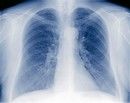

Tuberculoza este o boala infectioasa determinata de un anumit fel de microbi: bacili tuberculosi sau bacili Koch. Cel mai frecvent afecteaza plamanii (peste 90% din cazuri),dar si alte organe (ganglioni, oase, meninge, rinichi etc). Se poate prezenta sub forma latenta (bacteria exista in organism, insa nu poate fi raspandita si altor persoane) sau activa (simptomele sunt prezente, permitand raspandirea infectiei prin tuse, stranut cand se elimina picaturi de saliva in aer). Printre simptomele

Ce este boala tuberculoasa: bacilii se inmultesc in organismul unei persoane, ceea ce va duce la aparitia simptomelor bolii. Bacilii se inmultesc lent, distrugand treptat tesutul unde se afla. In lipsa tratamentului apar adeverate "gauri" in plamani, numite caverne tuberculoase. In momentul in care plamanii sunt grav afectati ei nu isi mai pot indeplini functia si apare decesul (evolutia fiind de regula de cativa ani de la declansarea bolii)